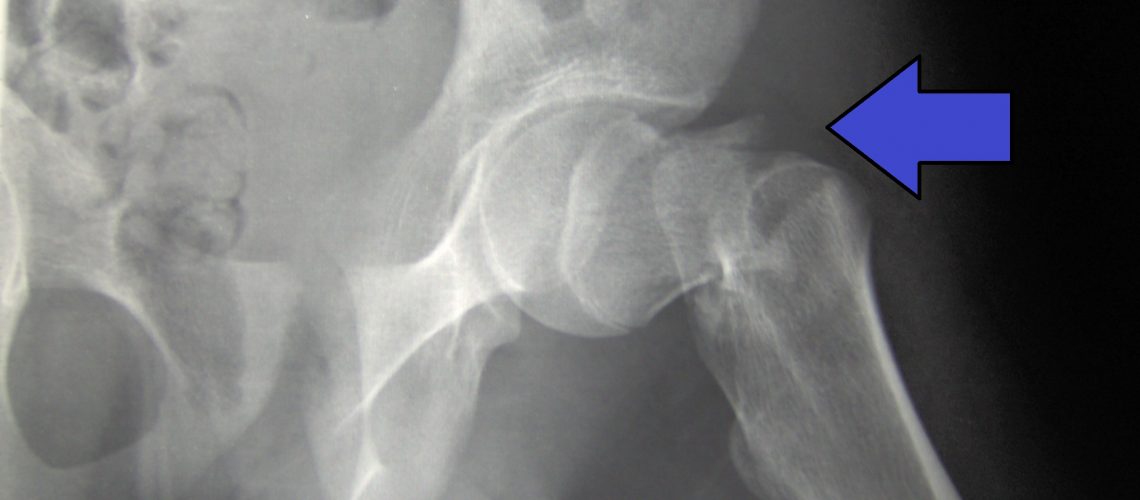

Most hip fractures occur at the femur, the long bone that extends from the pelvis to the knee. The part most affected by fractures is the neck of the femur, which is at the top of the bone, just below the femoral head.

The fracture can also occur in the intertrochanteric region, which is somewhat lower than the hip joint, in the portion of the upper femur that juts outward.